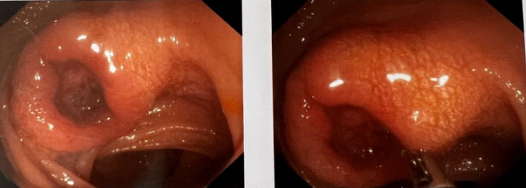

年过中旬的乔先生近30年来饱受大便习惯伴性状改变的困扰,大便不成形、稀,频次多、量少,偶有大便带血,色暗红。到医院做电子肠镜等相关检查后,发现肠腔已经明显狭窄,更没想到同时检查出了乙状结肠肿块,但是乔先生自己感觉一点征兆也没有,怎么一个月突然就得了结肠癌呢?

经过全面的检查和评估,张健主任最终决定,根据患者的具体情况,为其制定和实施个体化的精准治疗快速康复方案。在相关科室的密切配合下,由张健主任带领普通外科团队为乔先生成功实施了腹腔镜下乙状结肠癌根治术。在普通外科医护人员的精心护理下,乔先生恢复迅速,术后11天顺利出院。